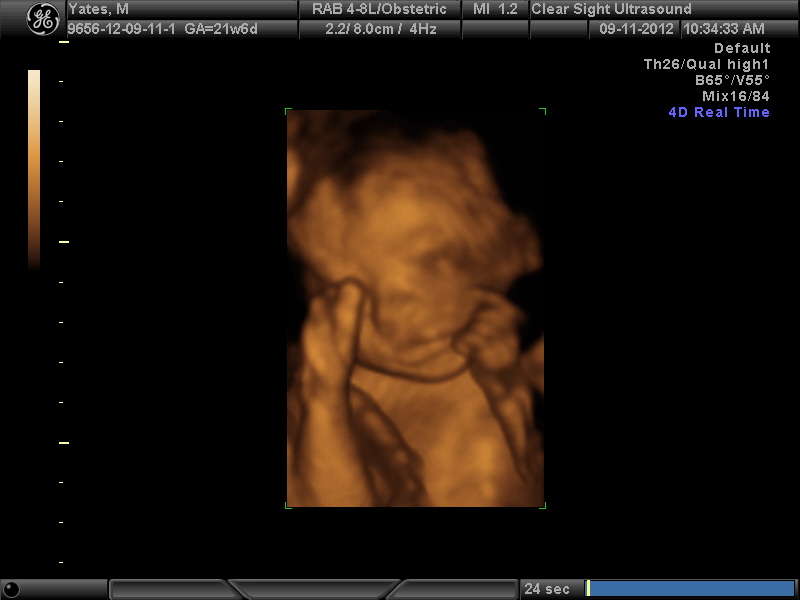

After having an awful 20 week ultrasound experience, where I barely got to see the baby 15 seconds, I paid to get one of those fancy 4d ultrasounds. My mom was visiting her sister in Central Virginia so I scheduled it down there so that she could go with me. It was amazing!! And the results are in....

It's another little princess!